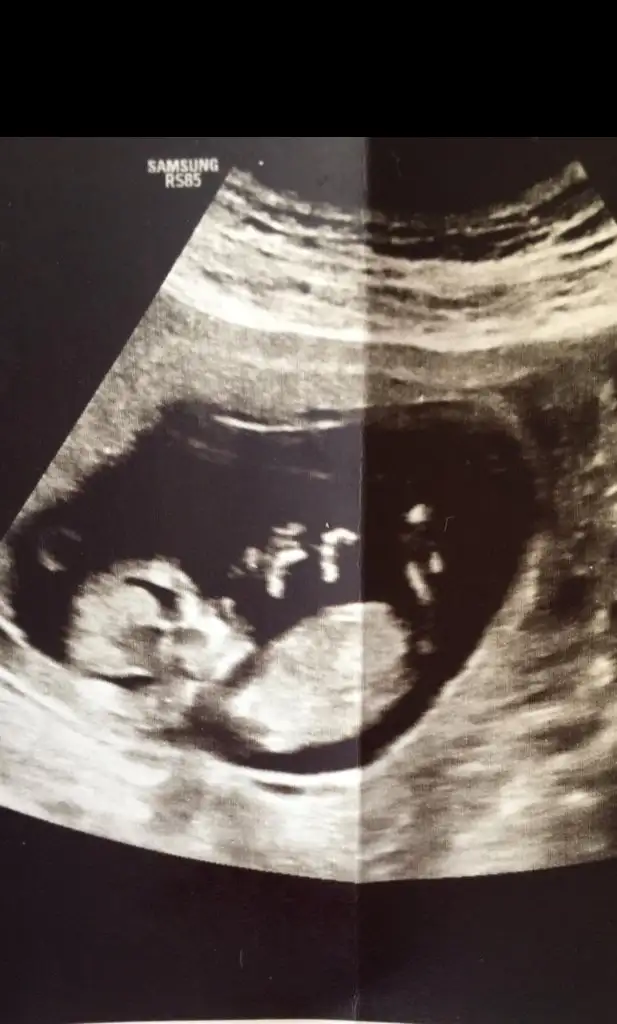

dr soylemeden siz gorun genital nub teorisi ( bebegin cinsiyeti)

Tahmininiz nedir

• 20220929_121220.webp

20220929_121220.webp

12,2 KB · Görüntüleme: 102